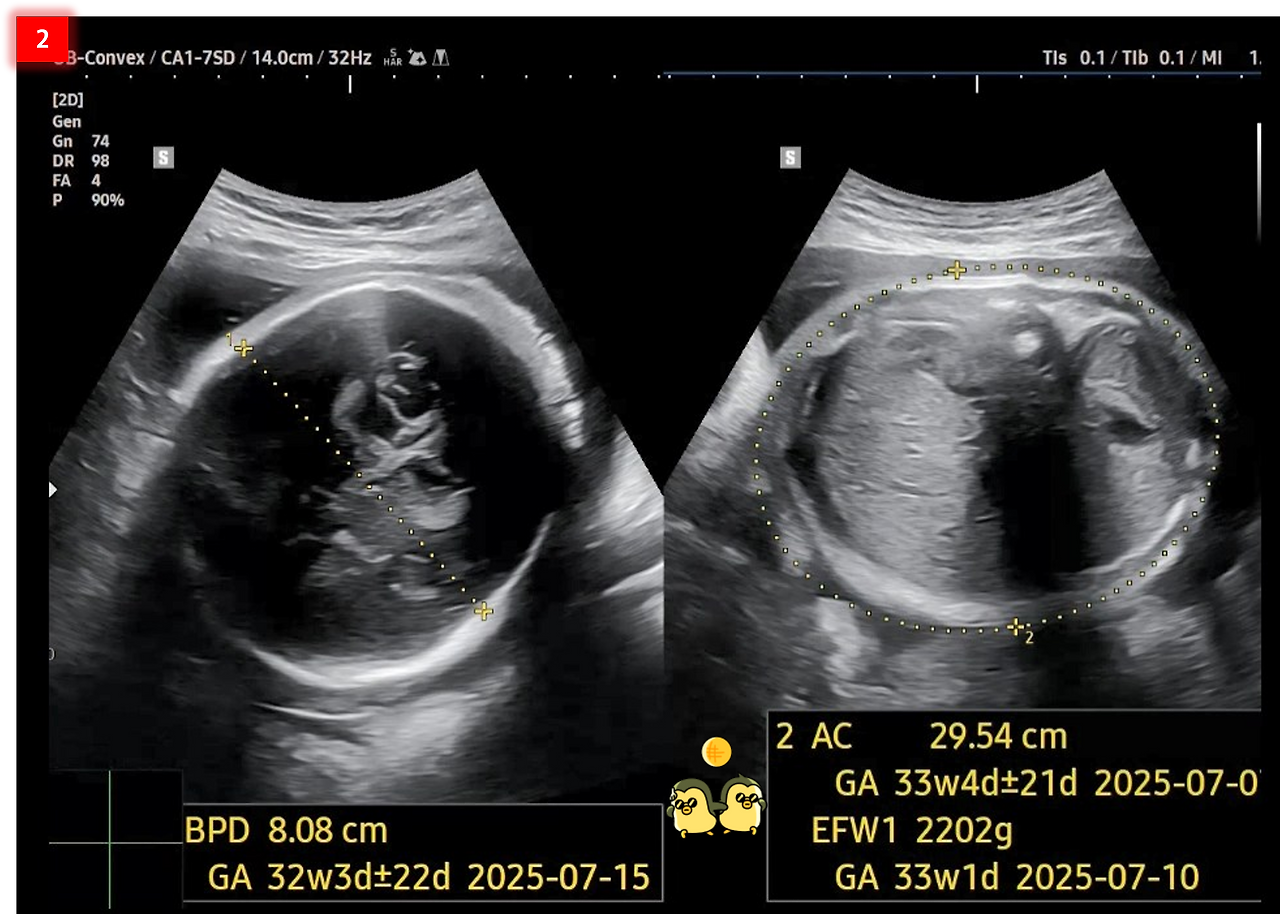

3. 허벅지 뼈의 길이(FL: Femur Length)는 6.61㎝로 나옵니다. 평균을 보면 약 6.2㎝라고 하니 좀 큰 편입니다. 머리는 작고 다리는 긴 편이라 모델형 태아인 것 같다고 아내는 이야기하네요.

그리고 태야 추정 체중(EFW: Estimated Fetal Weight)은 약 2.2㎏로 나옵니다. 차병원에서 제공하는 임신 주 수별 태아 몸무게 표를 보니, 평균에 속한다고 나오네요. 초음파 검사 시 태아의 머리직경과 복부 둘레의 길이를 재면, 기계에서 계산하여 보여준다고 합니다. 그런데 태아의 배나 머리의 길이를 정확하게 재는 것이 어려울 때가 많아서, 태아 몸무게도 오차가 크다고 합니다. 평균 200~300g의 오차가 나기는 하는데, 때로는 500g 이상 차이가 나는 경우도 있다고 하네요.

FL&EFW.png